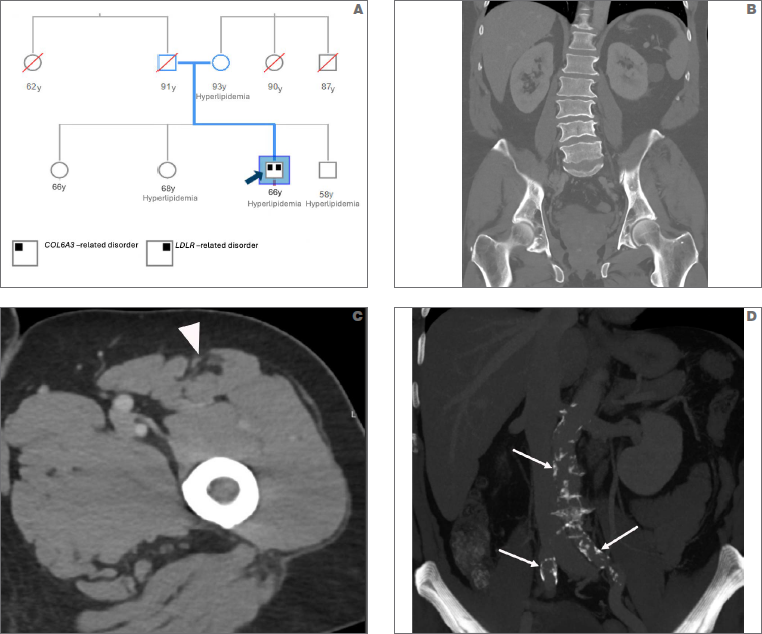

The patient had no known personal history of contractures or gait abnormalities. His family history includes multiple 1st degree relatives with hyperlipidemia, but he has no known family history of muscle diseases (Fig. 1A). The patient’s myopathic symptoms began at age 56. The genetic tests demonstrated COL6A3-RD [due to a heterozygous pathogenic variant, c.399del (p.Ala134Leufs*14)] and LDLR- related familial hypercholesterolemia [due to a heterozygous pathogenic variant, c.781T > A (p.Cys261Ser)]. COL6A3 [NM_004369.4] c.399del is a novel frameshift variant that creates a premature translational stop signal (p.Ala134Leufs*14), which is predicted to result in an absent or disrupted protein product. Haploinsufficiency of COL6A3 has been associated with COL6A3-RD, Bethlem myopathy 1,2. COL6A3 c.399del (p.Ala134Leufs*14) fulfills the PVS1 (very strong), PM2 (moderate, applied at supporting level), pathogenicity criteria of the American College of Medial Genetics (ACMG) and the Association for Molecular Pathology (AMP) variant classification system 3, hence was classified as a pathogenic variant. LDLR [NM_000527.4] c.781T > A (p.Cys261Ser) variant fulfills the PS4 (strong), PM1, PM2,PM5, and PP3 (supporting) criteria of the ACMG/AMP variant stratification system, hence was classified as a pathogenic variant. The patient’s relatives were unavailable for family variant testing for the COL6A3 and LDLR variants. The concurrent germline presence of COL6A3 c.399del (p.Ala134Leufs*14) and LDLR c.781T > A (p.Cys261Ser) resulted in a composite neuromuscular phenotype with cardiometabolic and cerebrovascular consequences. CT of the abdomen showed scoliosis (Fig. 1B), anterocentral rectus femoris muscle atrophy (Fig. 1C) consistent with Bethlem myopathy 4, and atherosclerotic disease of the aorta and iliac arteries (Fig. 1D) in the context of LDLR-related hypercholesterolemia.

Figure 1. (A) Pedigree showing multiple 1st degree relatives with hyperlipidemia. Coronal CT image of the abdomen (B) shows dextroconvex lumbar scoliosis with associated multilevel degenerative disc disease. Axial CT image of the left thigh (C) shows anterocentral atrophy of the rectus femoris muscle (arrowhead) characteristic of Bethlem myopathy. Coronal CT maximum intensity projection (MIP) image (D) shows extensive atherosclerotic disease (arrows) involving the aorta and bilateral common iliac arteries.